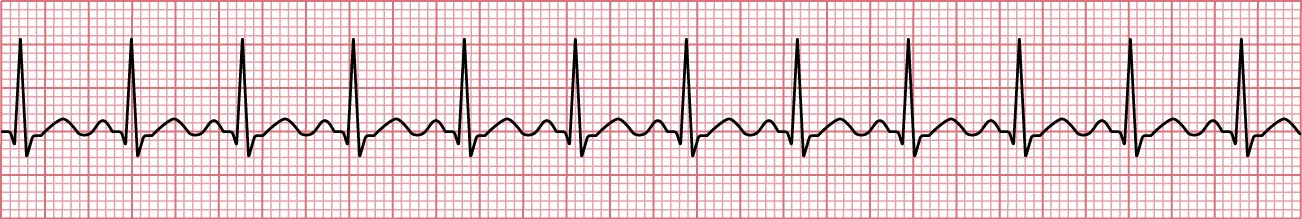

Ventricular disturbances are the most serious dysrhythmias and require prompt, emergent intervention. A ventricular tachycardia is when the ventricle beats rapidly at 150 to 200 bpm with wide QRS complexes (greater than 0.12 seconds) and no discernible PRs or P waves (Figure 12.16). A ventricular fibrillation is slightly faster than ventricular tachycardia with rates over 200 bpm (Figure 12.17). A classic finding in ventricular fibrillation is a chaotic baseline with no discernible QRS, PRs, or P waves. Patients with ventricular tachycardia may be able to report subjective feelings of fluttering, fatigue, and near syncope. The patient will be diaphoretic and have weak pulses. In severe cases, they can lose perfusion and have syncope. Ventricular fibrillation is considered a cardiac arrest as patients will lose consciousness and require advanced cardiac life support. Causation of these dysrhythmias can be from myocardial infarction, heart failure, electrolyte disturbance, illegal substance abuse, shock, or medications.

Sinus rhythm showing ventricular tachycardia with fast rate, no discernable P waves, and wide QRS.

Figure 12.16 In ventricular tachycardia, the rate is fast, there are no discernible P waves, and the QRS is wide. (attribution: Copyright Rice University, OpenStax, under CC BY 4.0 license)